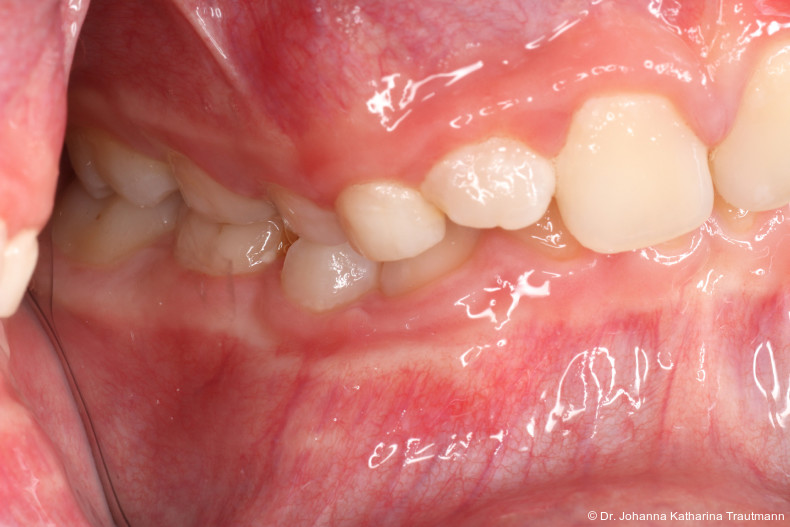

Das Fernröntgenseitenbild zeigte eine skelettale Klasse IIAnomalie mit einem Wits von 5,6 mm, bei einer tiefen Konfiguration (ML NL = 16,5°) mit bialveolär retrudierten Fronten (OK1NA = 5,9°; UK1NB = 10,4°), was sich auch in der Modellanalyse widerspiegelte. Hier zeigte sich zudem ein schmaler Oberkiefer mit multiplen Kippungen und Rotationen in der Front, einem hypoplastischem 22 sowie einer Mesialwanderung des 16. Des Weiteren zeigte sich eine asymmetrische Bisslage mit 1 PB distal rechts und ½ PB distal links bei einem Overjet von 2,5 mm sowie einem Overbite von 5 mm. Während im Unterkiefer bereits die zweite Zahnwechsel phase begonnen hatte, zeigte sich im Oberkiefer noch kein Wechsel in den Stützzonen. Gerade bei Patienten mit Spaltbildungen ist eine engmaschige Überwachung des Durchbruchs der oberen Eckzähne essenziell. Während bei der Allgemeinbevölkerung die Prävalenz von verlagerten Eckzähnen bei ca. 2,8 Prozent liegt2, ist diese bei Patienten mit Lippen-Kiefer-Gaumen-Spalten um den Faktor 10 erhöht.3, 4 Als klassische Risikofaktoren gelten zudem Platzmangel, transversale Enge aber auch Fehlstellungen, Nichtanlagen oder Hypoplasien der zweiten Schneidezähne. Diese übernehmen normalerweise die Funktion der Leitschiene für den S-förmigen Durchbruch der Eckzähne. Im vorliegenden Patientenfall kommen also mehrere Risikofaktoren für eine Verlagerung zusammen, was die rechtzeitige Diagnostik zur Abklärung einer Durchbruchsproblematik rechtfertigt. Da im Spaltbereich auch zusätzlich ein ausgeprägtes Knochendefizit vorliegen könnte, sollte auch immer die Option einer sekundären Osteoplastik abgewogen werden, deren Indikation und Timing optimal zum Durchbruch der Canini angepasst werden sollte.5

Nach transversaler Nachentwicklung der Maxilla mittels GNE nach Veltri wurde der Zahn 23 geschlossen freigelegt und an einem individualisier ten TPA nach distal angebunden. Zur Aufrichtung der Front und Mesialisierung des hypoplastischen Zahnes 22 kam zusätzlich eine 2x3Mechanik zum Einsatz. Eine rein translatorische Bewegung eines Zahnes ist auch mit einer festsitzenden Apparatur schwer zu erreichen, da der Kraftansatzpunkt nicht identisch mit dem Widerstandszentrum des Zahnes ist.7 Diese Problematik kann einerseits durch das Einbringen eines Versetzungsmomentes adressiert werden, andererseits durch eine Verlagerung des Kraftansatzpunktes. Angelehnt an den von Hong et al. beschriebenen Power Arm 8 wurde hierfür palatinal an Zahn 22 ein cranial gerichteter Hook angebracht (Abb. 3). Da Zahn 22 aufgrund seiner Hypoplasie eine verkürzte Wurzel aufwies, konnte so die Distanz zwischen Widerstandszentrum und Kraftangriffspunkt effizient reduziert werden. Eine weitere biomechanische Schwierigkeit stellte das geringe Alveolarknochenangebot im Spalt bereich mesial von 22 dar. In Bereichen mit Knochendefizit verschiebt sich das Widerstandszentrum nach apikal und wie in diesem Fall zusätzlich nach distal.9, 10 Um dem erhöhten Risiko für Kipp bewegungen entgegenzuwirken, muss hier besonders auf die Steuerung des M/F-Quotienten geachtet werden. Der vestibulär durchgebrochene Zahn 13 benötigte keine Freilegung. Um seine korrekte Einstellung zu ermöglichen, wurde die Mesialwanderung des Zahnes 16 mithilfe des TPAs korrigiert sowie eine Mittellinienkorrektur nach links mittels 2x3 Mechanik durchgeführt.

Im Rahmen der Multibrackettherapie wurde bewusst der Zahn 13 aus dem Hauptnivellie rungsbogen ausgelassen, um Kippungen und Asymmetrien im Zahnbogen zu vermeiden. Der Zahn 23 wurde locker mit einer Distanz ligatur angebunden, um eine weitere Bewegung nach vestibulär zu erreichen. Auf einem 0.019" x 0.025" Stahlbogen erfolgte anschlie ßend mittels Umgehungsbiegung sowie eines Overlaybogens (0.014" NiTi) die Integration des Zahnes 13 in den Zahnbogen. Die Zwischendiagnostik nach einem Jahr festsitzender Behandlung zeigte eine gelungene Bisshebung bei guter Nivellierung des Okklusionsplanums und orthoaxialer Einstellung der Frontzähne. Die Zahnbögen präsentierten sich harmonisch ausgeformt, es zeigte sich jedoch eine verbleibende Torqueproblematik an bei den Oberkiefereckzähnen. Nach Freilegung und Einstellung verlagerter Eckzähne ist eine korrekte Torque und Angulationssteuerung häufig eine Herausforderung. Während vestibulär verlagerte Zähne zu gingivalen Rezessionen neigen, behalten palatinal verlagerte Zähne oft ihre palatinale Wurzelstellung bei.13, 14 Die genutzte MBTPrescription der Brackets bietet die Möglichkeit, zwischen +7°, 0° und –7° Torque zu wählen.15 In einem 0.022" System ist bei Verwendung eines 0.019" x 0.025" Bogens jedoch mit einem Torqueverlust von etwa 10° zu rechnen.16